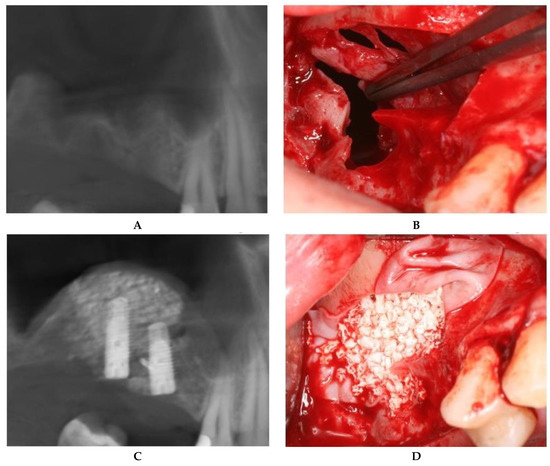

For large or multiple perforations, a single large pericardium membrane is placed in intimate contact on the elevated sinus membrane covering beyond the margin of the perforated area/s. In this study, collagen membranes with a low resorption rate (CopiOs Pericardium Membrane, Zimmer Biomet, Warsaw, IN, USA) were used to seal the perforated Schneiderian mucosa (Figure 1).

Large (more than 10 mm) or multiple perforations usually occur in thin, fragile sinus membranes with reduced elasticity. The remaining mucosal tissue between multiple perforations makes it impossible to suture without additional strain on the membrane. In addition, medially positioned perforations from the osteotomy contour lead to reduced access and visibility, which hindered correct suturing of the mucosal margins. For these reasons, the treatment of choice in this type of Schneiderian membrane tear is to seal with a pericardium membrane in order to provide an inside lining (Figure 1).

Figure 1. Schneiderian membrane sealing technique with collagen membrane coverage. (A) Preoperative CBCT image. (B) Large, multiple Schneiderian membrane perforations. (C) Bone graft placed in the collagen membrane “pouch”. (D) Postoperative CBCT after implant placement.